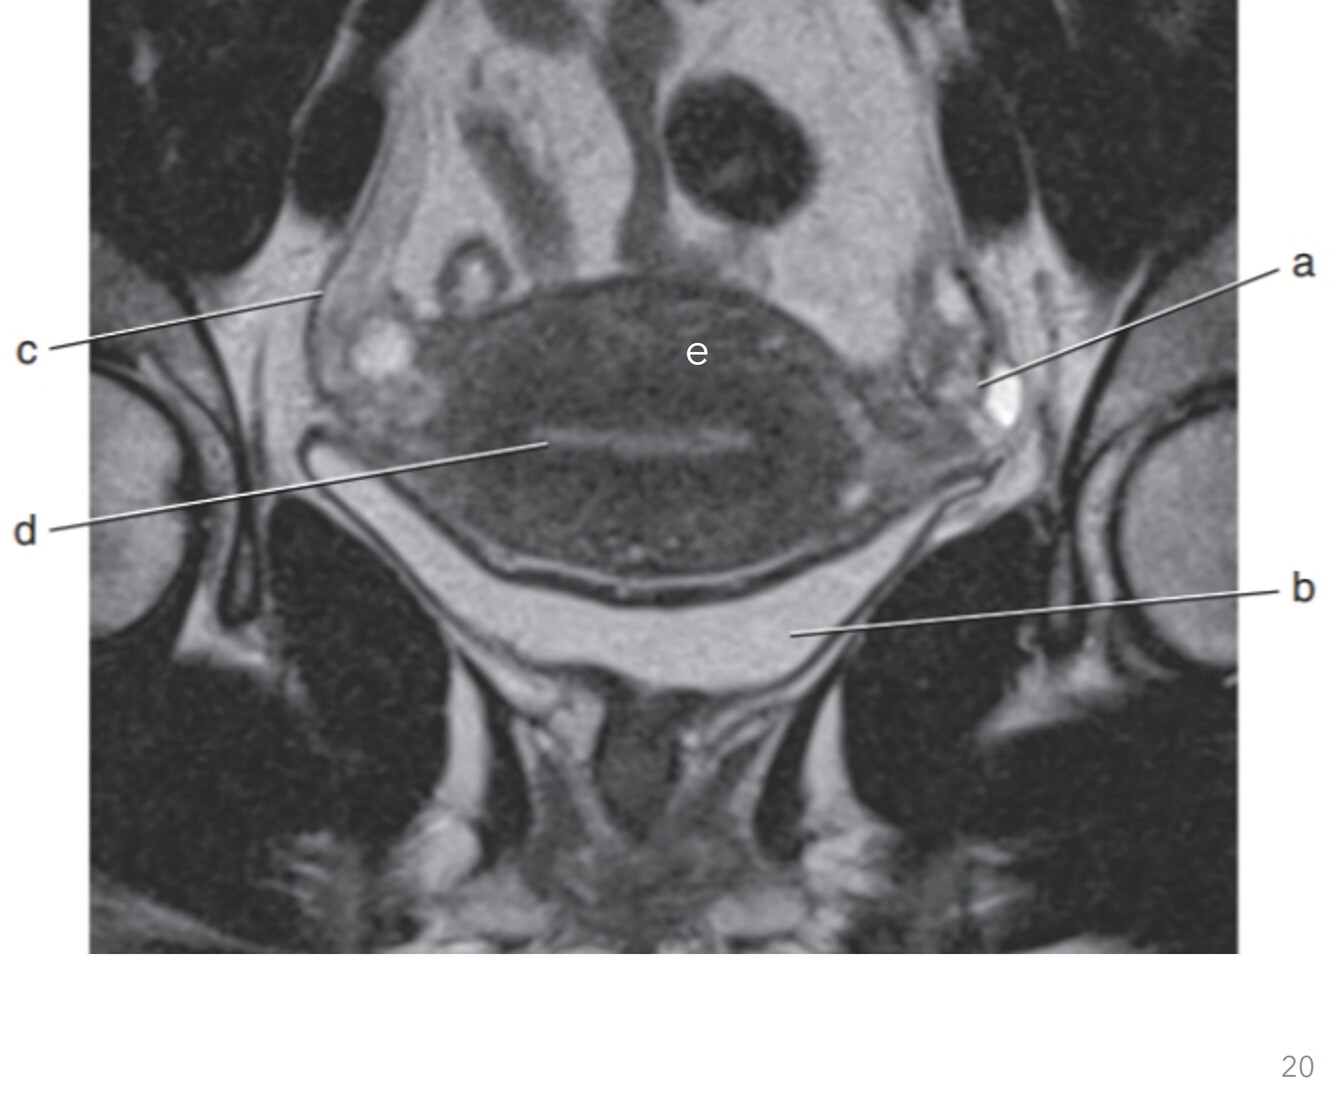

20

Q

Label a-d

A

a. Pubic symphysis

b. Prostate gland

c. Rectum

d. Coccyx